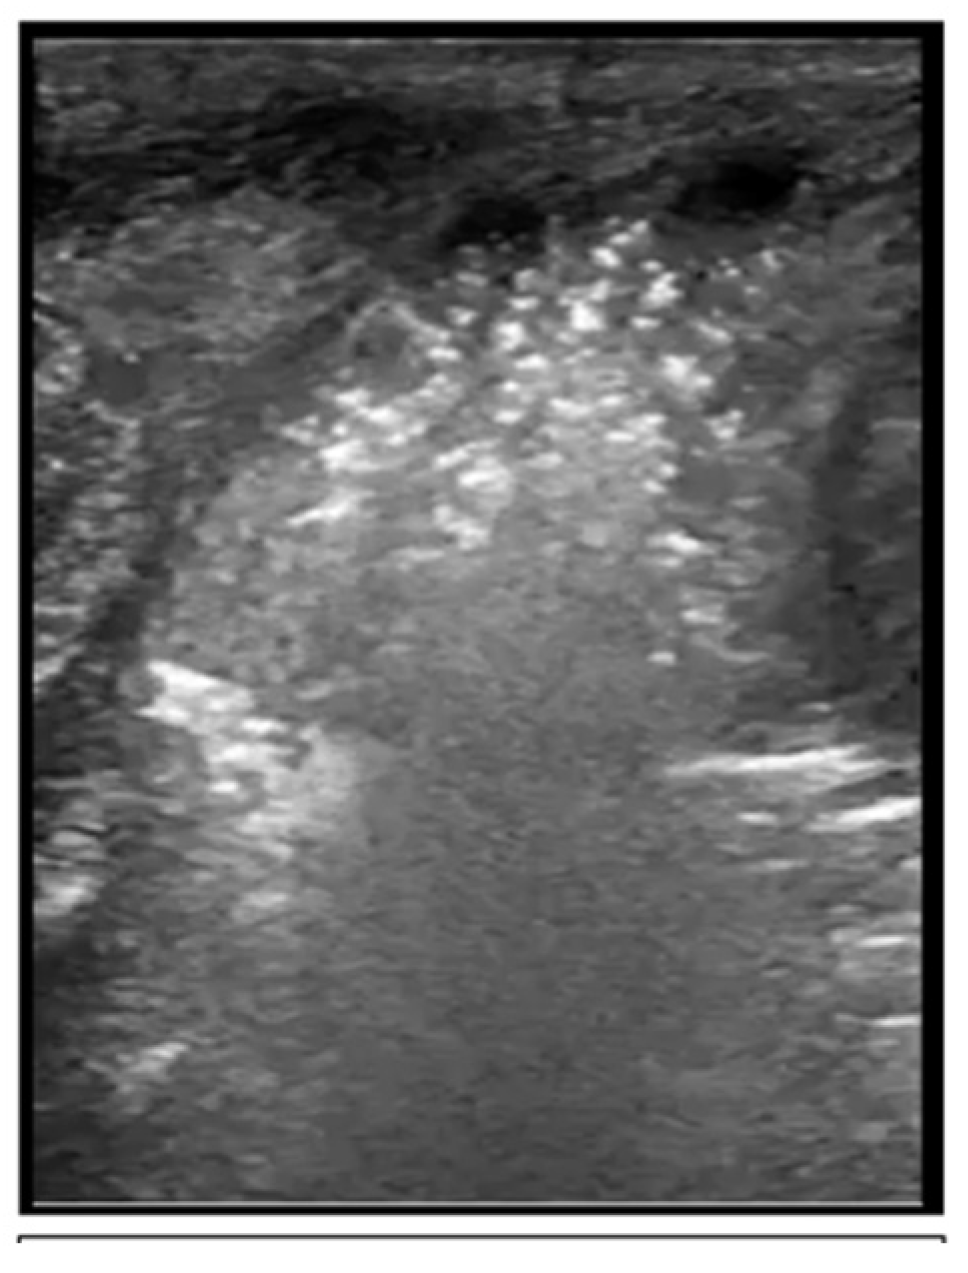

2.5. Respiratory Distress Syndrome

Predicting the Need for Intervention with Respiratory Distress Syndrome